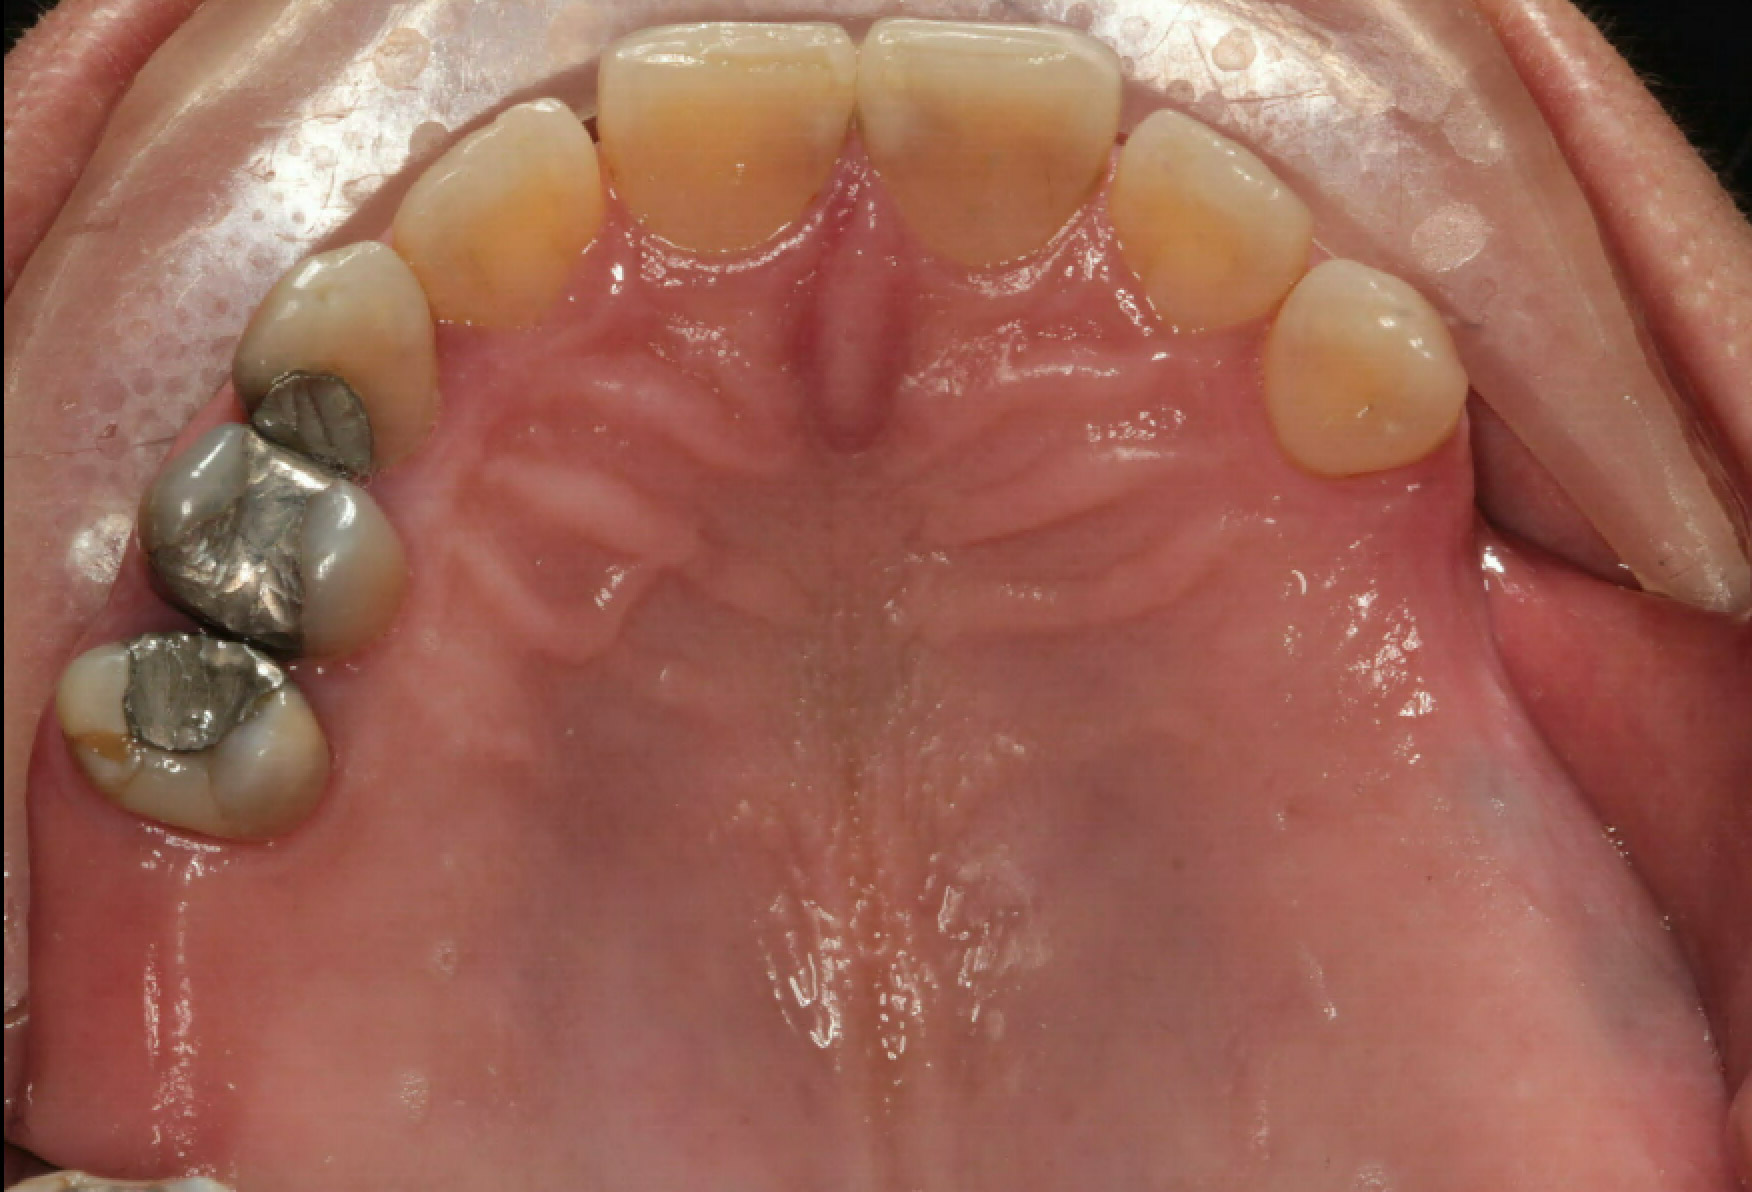

VII. INTRA ORAL PICTURES

Intra Oral Pictures (1)

(Treatment in progress)

Intra Oral Pictures (2)